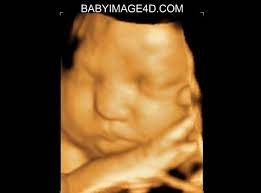

You'll still get a look at their little face. I'm only at 31 weeks, but i had that 4d/3d u/s and yes, baby looked totally deformed. Best between 24 and 36 weeks. 20 minute 2d/3d & 4d ultrasound. Baby's first photos 112 e.

Baby impressions is an elective 3d 4d ultrasound imaging facility. Fetal measurements (by request) hear & see baby's heartbeat. 3d & 5d ultrasound images and 4d ultrasound video can be obtained at any stage. Baby's estimated weight and position. 30 weeks is best for 3d/4d images of what your baby will look like after it is born. Water can improve the quality of an ultrasound. At this stage, the baby has put on some weight and filled out to make features more visible, yet still enough fluid in front of baby's face to obtain great images. You'll notice that what you see varies a lot by the number of weeks of gestation. It was a very special day for my husband and i. In addition to 3d 4d ultrasound, baby bloom is known for our spectacular hd live ultrasound imaging. We do not perform medical ultrasounds. When i was 31 weeks i went back for our first 3d/4d ultrasound and it was even more special being able to see my son's face for the very first time. Book now *free rescan if face can't be seen at all.

$15 coupon towards any future hd ultrasound packages purchased during the same pregnancy; However, there are certain instances where you may find yourself having an ultrasound at this gestational age. 30 weeks is best for 3d/4d images of what your baby will look like after it is born. 20 minute 2d/3d & 4d ultrasound. Your baby has to hold very still so that the high frequency sound waves have time to form around your baby's features.